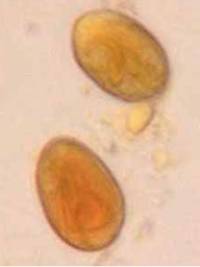

- Kotflotation

- Indikation: Würmer, Giardien, Kokzidien

- Durchführung: Flotation in Zinksulfatlösung mit darüber liegendem Deckglas für 10 Minuten

- Sammelkotproben wesentlich aussagekräftiger, da Wurmeiern intermittierend ausgeschieden werden